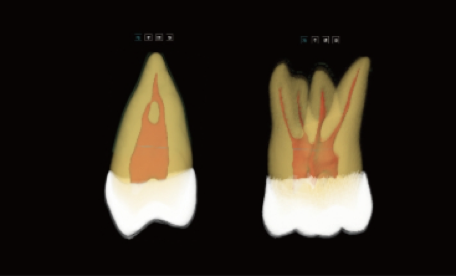

Tecnologia Inovadora Root-Bone Glass

Suporta o posicionamento manual dos dentes, a remoção dentária e a observação tridimensional da câmara pulpar.

Permite o planeamento imediato de extrações e implantes.

Análise Dentária 3D Abrangente: segmentação completa do dente com medições automáticas, planeamento do percurso de acesso e avaliação precisa de cáries.

Visualização Endodôntica Avançada: observação 3D de cáries interproximais, defeitos estruturais e morfologia dos canais radiculares, garantindo que nenhum canal passa despercebido.

Segmentação Completa da Estrutura Dentária: realce automático do esmalte, dentina, polpa e estruturas periodontais, permitindo a visualização das alterações morfológicas.

Mapeamento Avançado dos Canais Radiculares: visualização clara dos canais MB2 e em forma de C, apoiando um tratamento endodôntico preciso e minimizando o risco de canais não detetados.